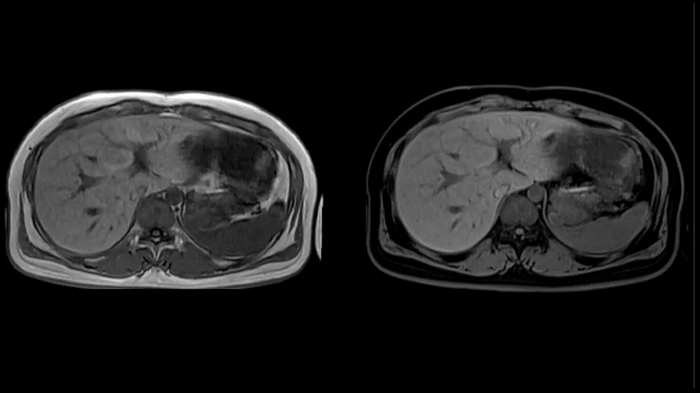

Abdomen

T1 VIBE Dixon with CAIPIRINHA

Get benefitted from Siemens Healthineers dedicated CAIPIRINHA acceleration to gain a complete abdominal volume within a single breath-hold. The Dixon technique offers outstanding fat water separation for a flawless representation of the abdominal anatomy.

MAC-ID: 7aaaa0165. Image Credit: Siemens Healthineers

Body diffusion imaging

For all-inclusive abdominal MR capabilities, outstanding quality diffusion imaging.

MAC-ID: 7aaaa0165. Image Credit: Siemens Healthineers

T2 BLADE

T2 motion insensitive abdominal imaging with BLADE results in outstanding outcomes, regardless of the orientation or if fat saturation is needed.

MAC-ID: 7aaaa0165. Image Credit: Siemens Healthineers